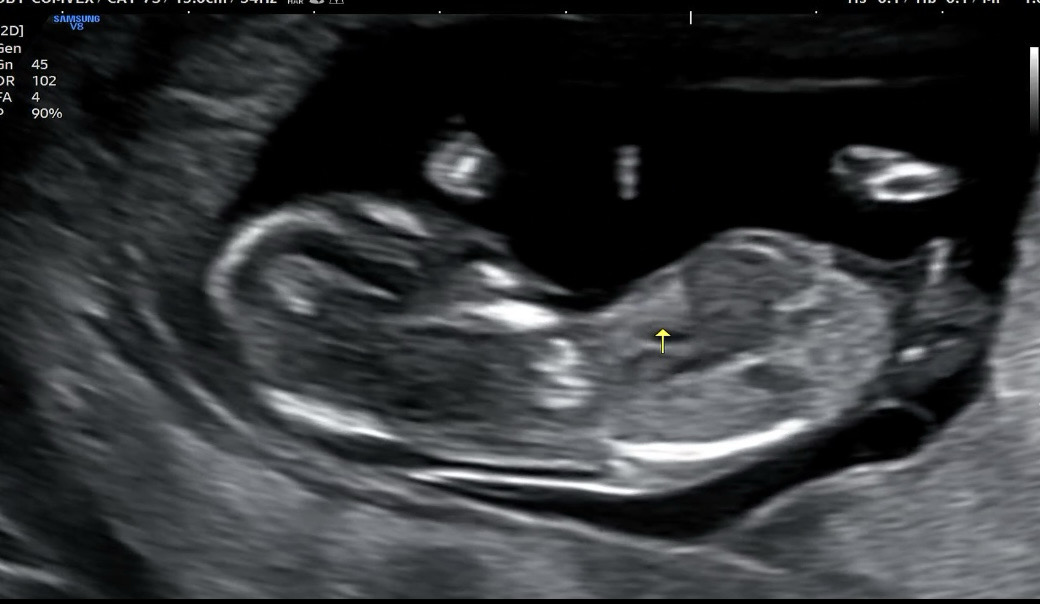

딸,아들 어떤가요?

각도법봐주세용~ 아들같아보이긴 해요..ㅎㅎ